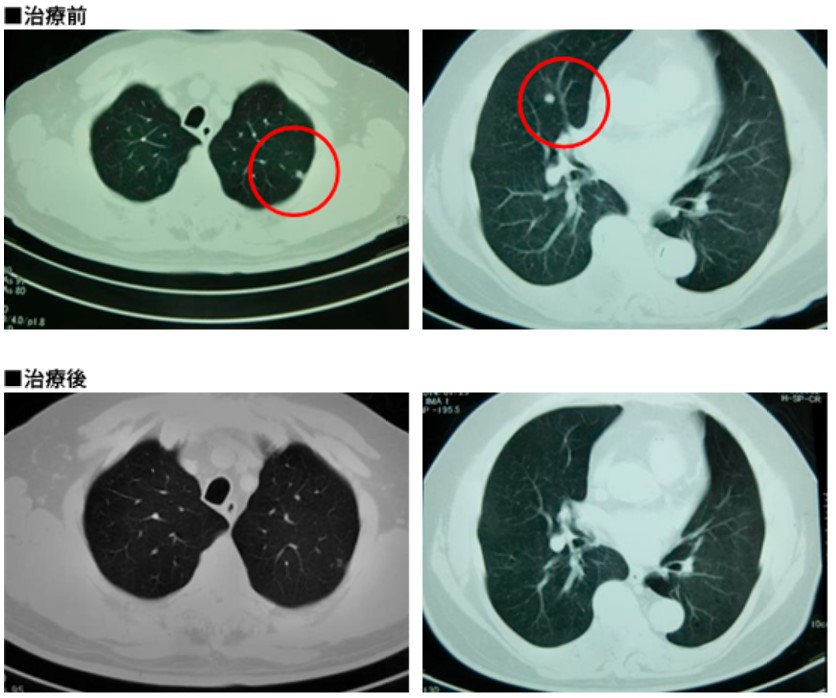

今年五月,上海的杨先生慕名前往全球肿瘤医生网寻求帮助。患者是他的父亲,今年79岁,5年前杨先生的父亲被诊断为S状结肠癌,手术后辅助化疗,病情一直稳定。直到今年3月,患者出现胸闷咳嗽症状,在当地权威肿瘤医院确诊为结肠癌手术后肺部转移。因患者年龄较高,为寻求最佳治疗方案,杨先生找到全球肿瘤医生网,经过专家初步评估,推荐患者接受日本安全无创的细胞免疫治疗。日本细胞免疫治疗第一人--阿部博幸教授为患者制定了树突细胞疫苗+活性NK细胞的治疗方案,一个疗程之后,患者肿瘤消失,肿瘤标志物正常。目前患者身体状态良好,密切随访中。